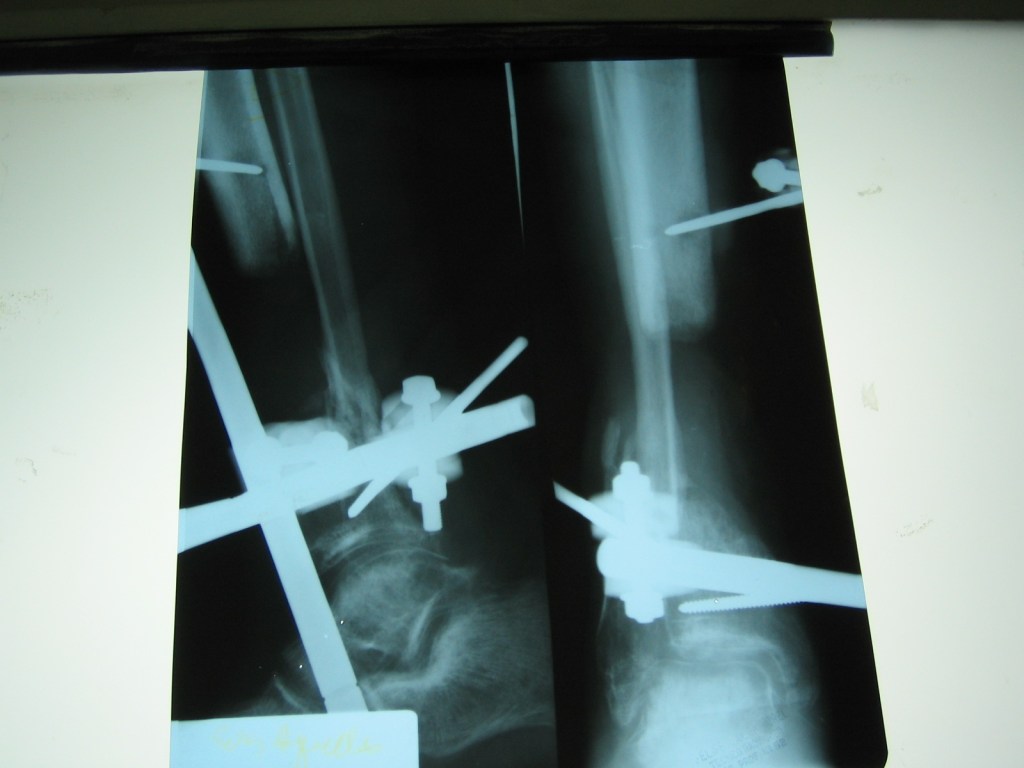

Deformidad grave de pierna con acortamiento oseo e infección

Luego de 10 años de cirugías en distintos centros del país , mi única opción era realizarme una amputación

Luego de consultar con el Dr Dratewka y su Equipo , me explicaron la necesidad de varias cirugías en etapas para tratar mi infección , corregir mi pie y devolver el largo de mi pierna

No tengo palabras para lo que me hicieron y ayudaron ,me sentí acompañada en todo momento y ahora puedo decir que no duden en hacer una consulta si tienen dudas sobres su problema